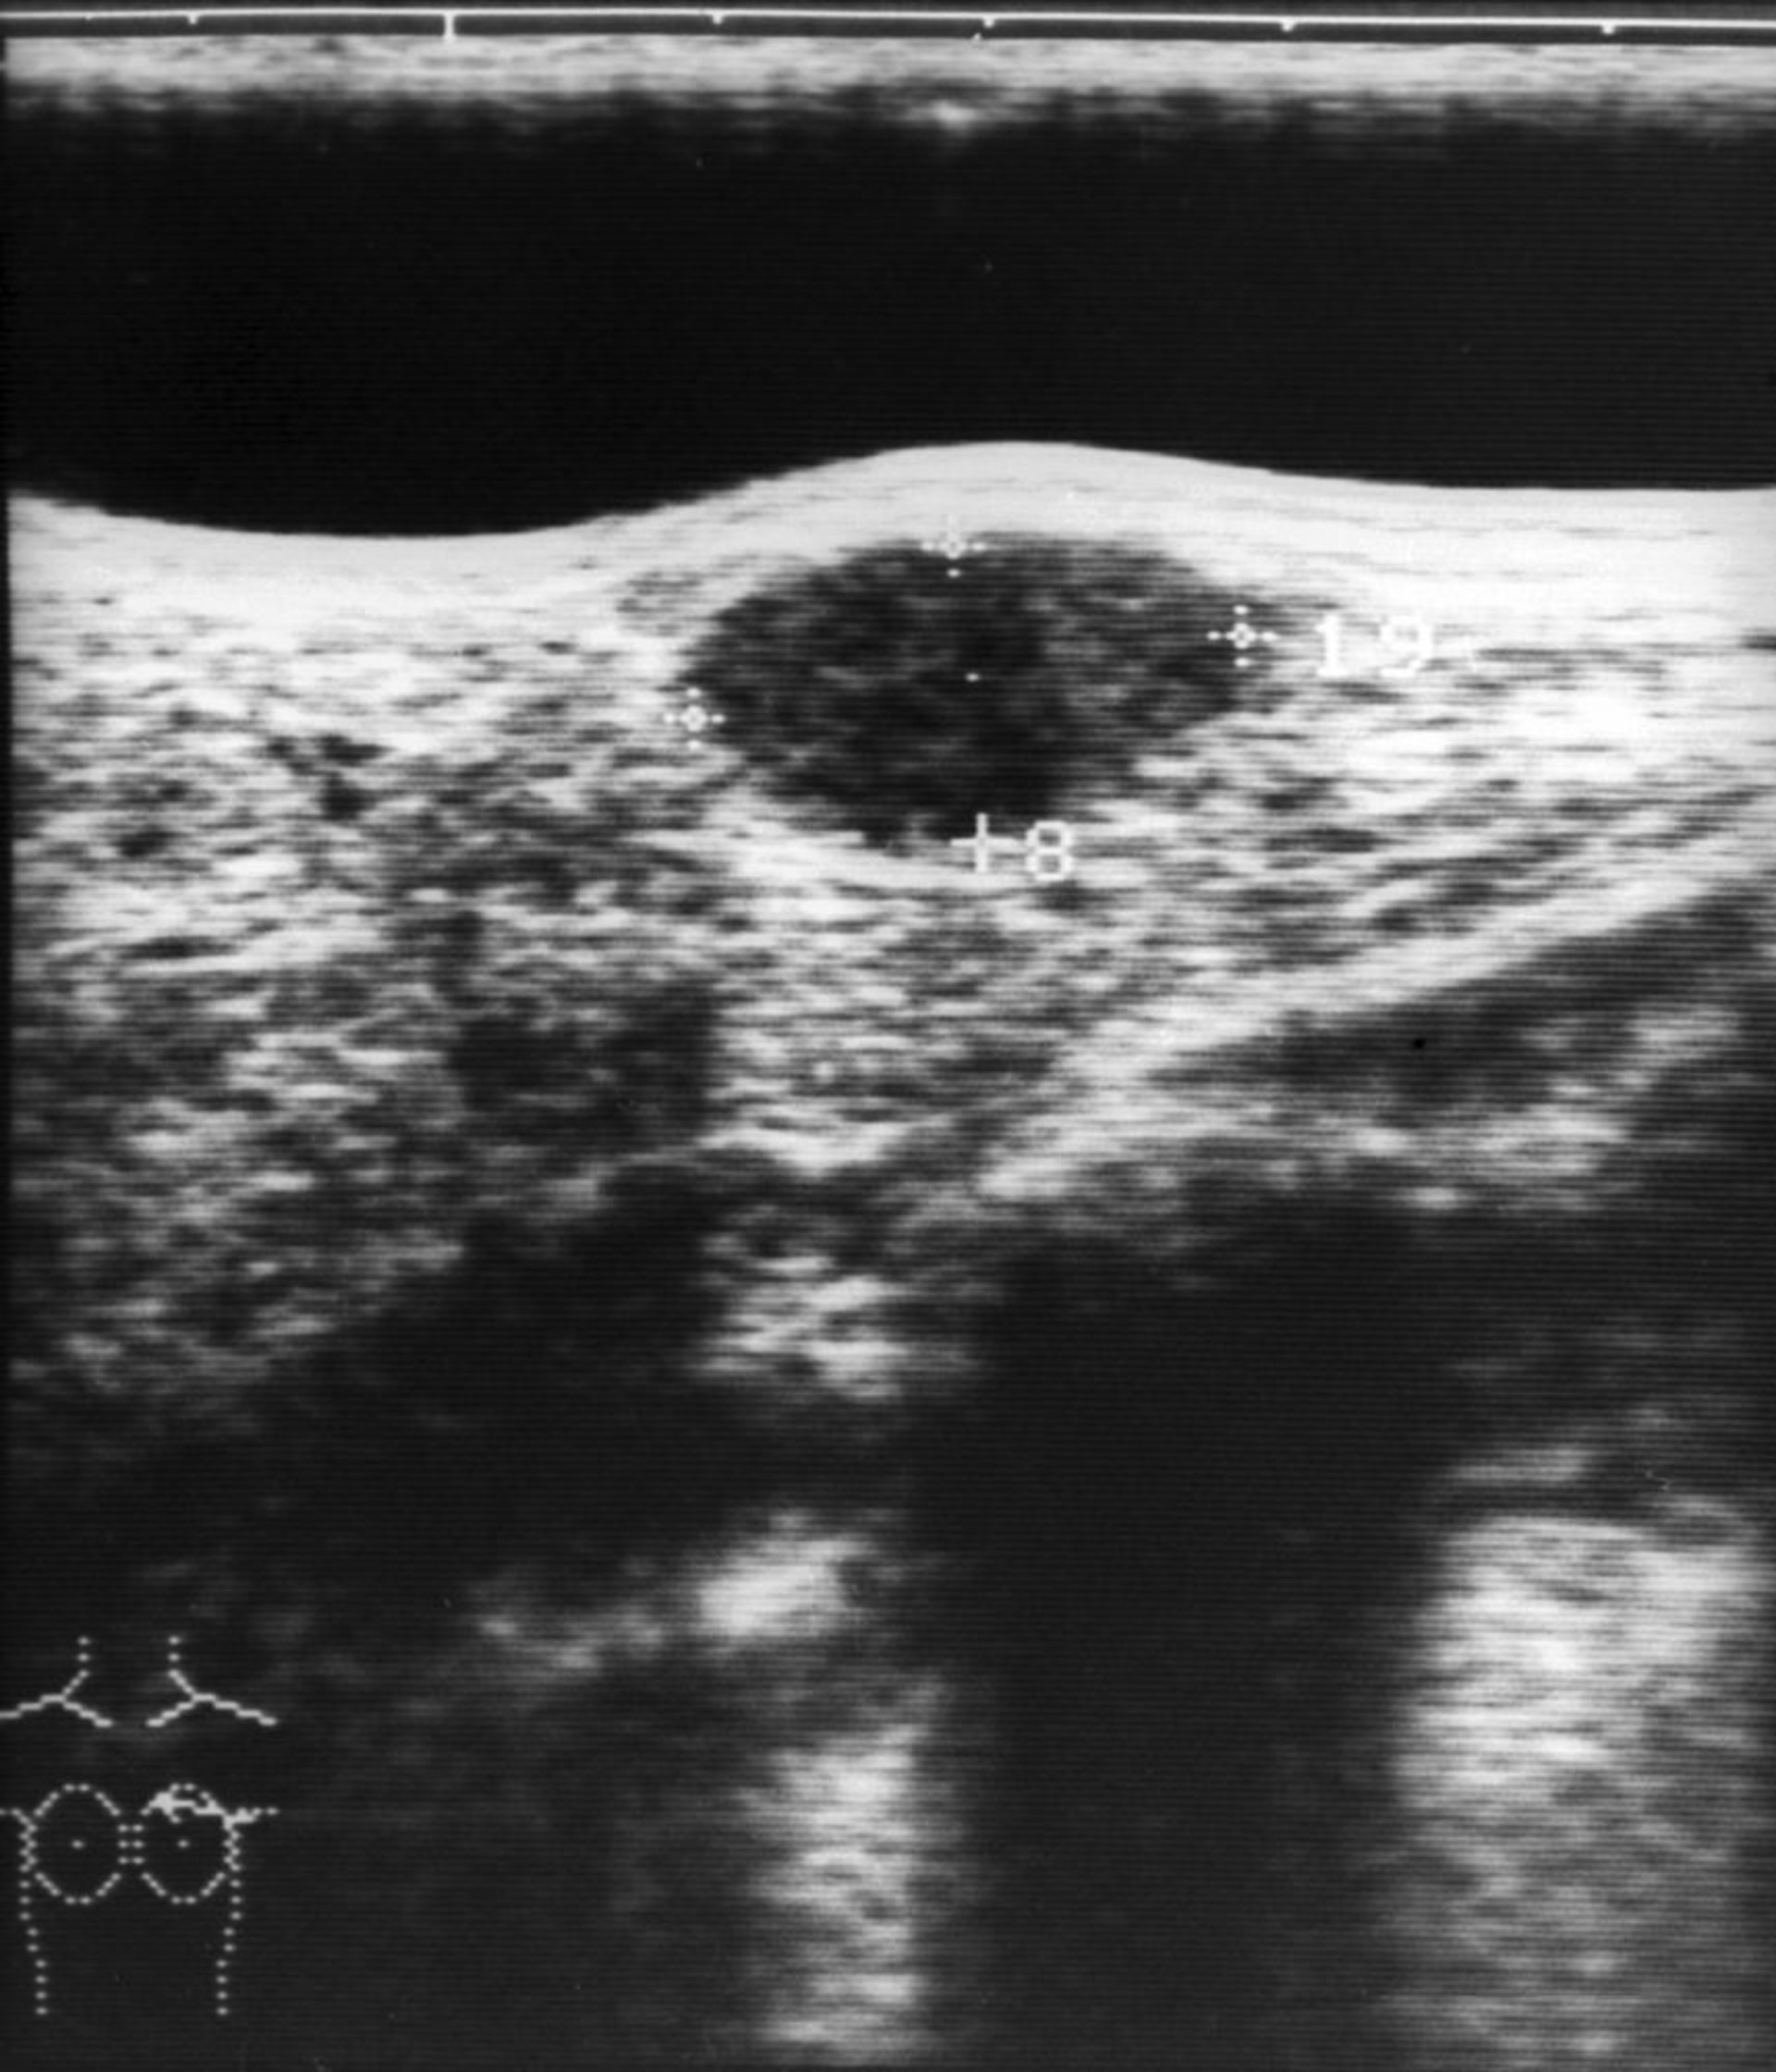

Questa immagine mostra un'ecografia di un fibroadenoma del seno (struttura ipoecogena ovale al centro superiore dell'immagine).